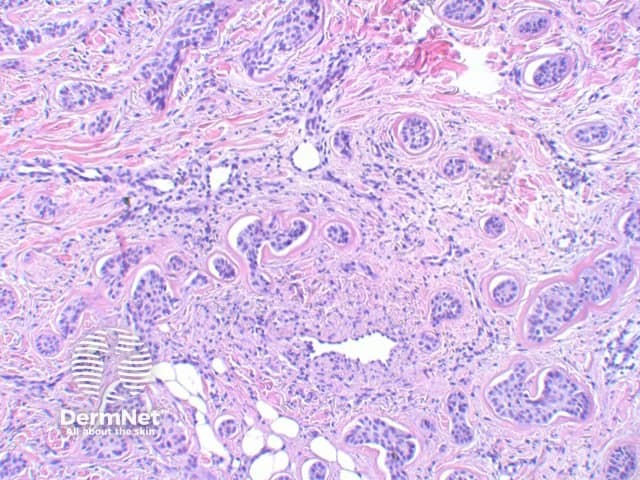

The key feature of basal cell carcinoma at low power magnification is of a basaloid epithelial tumour arising from the epidermis (figure 1). The basaloid epithelium typically forms a palisade with a cleft forming from the adjacent tumour stroma (figure 2). Centrally the nuclei become crowded with scattered mitotic figures and necrotic bodies evident (figure 3). A useful distinguishing feature from other basaloid cutaneous tumours is the presence of a mucinous stroma (figure 4). Some tumours may also show foci of regression, seen as areas of eosinophilic stroma with lack of basaloid nests.

Figure 2